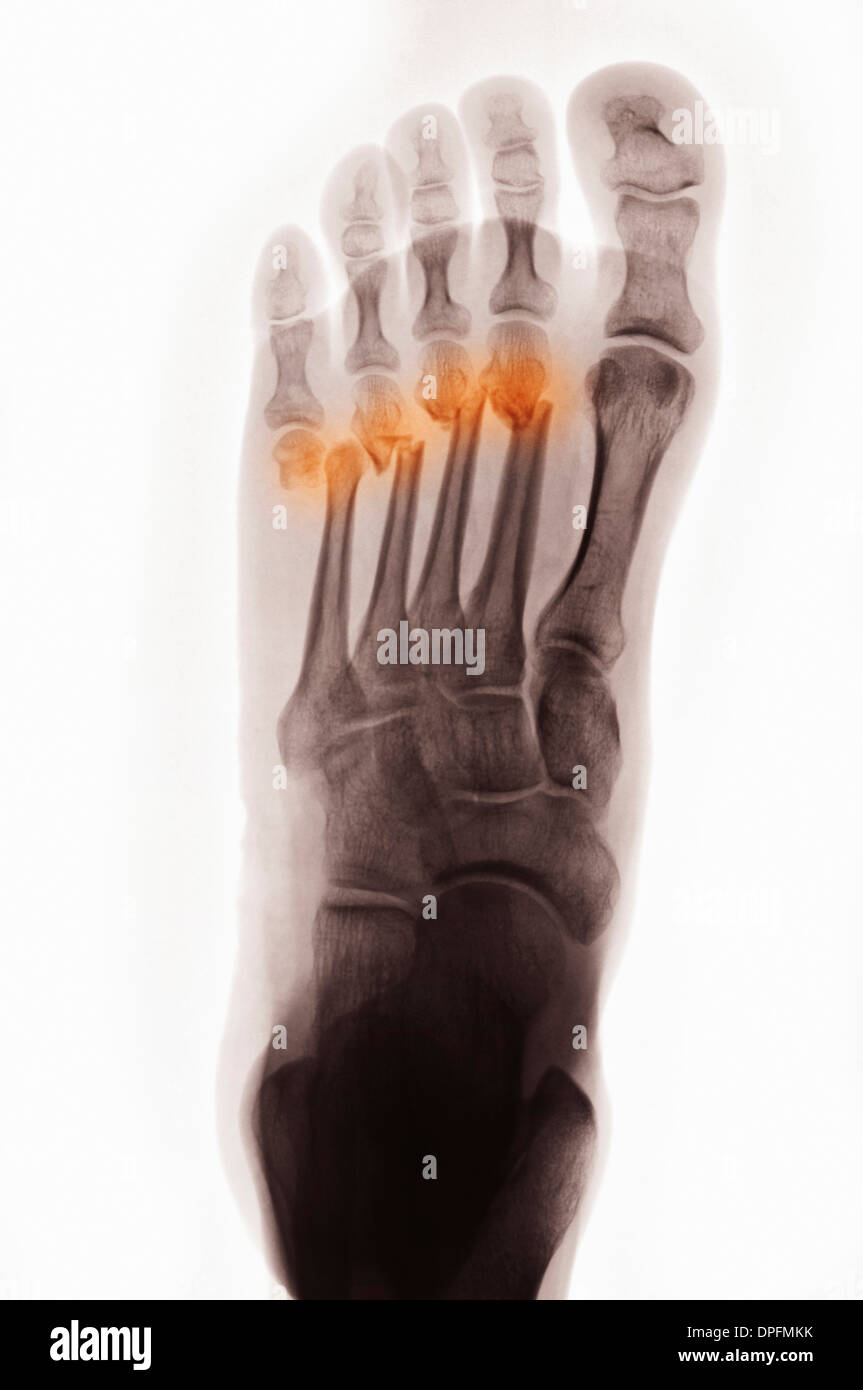

Xray of foot with fracture of metatarsal Stock Photo Alamy X Ray Metatarsal Fracture If you break a metatarsal, you might go to the emergency room or see your regular doctor. The proximal 5 th metatarsal is the site of a number of fractures. Metatarsal fractures are among the most common injuries of the foot that may occur due to trauma or repetitive microstress. Learn about the structure, function, and common types of metatarsal. X Ray Metatarsal Fracture.

X Ray Metatarsal Fracture . The proximal 5 th metatarsal is the site of a number of fractures. Displacement is usually minimal unless more than one metatarsal is fractured. Most metatarsal shaft fractures are oblique or transverse (figure 1a). Metatarsal fractures are among the most common injuries of the foot that may occur due to trauma or repetitive microstress. Learn about the structure, function, and common types of metatarsal fractures, such as dancer's fractures, jones fractures, and lisfranc injuries. If you break a metatarsal, you might go to the emergency room or see your regular doctor.